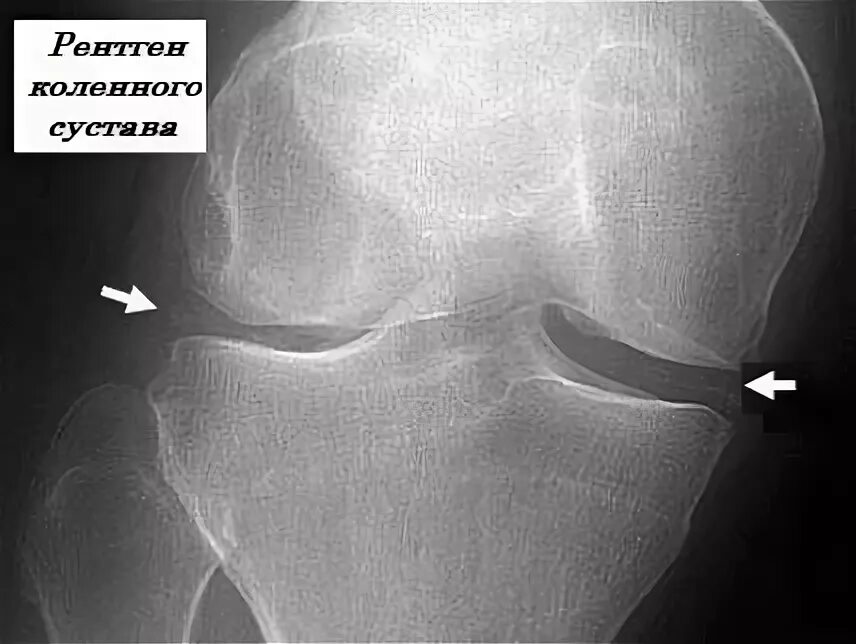

Лигаментоз коленного сустава рентген. лигаментоз тазобедренного сустава рентген. обызвествление в мягких тканях коленного сустава рентген. тендиноз тазобедренного сустава рентген.

Лигаментоз коленного сустава рентген. хондроматоз голеностопного сустава. лигаментоз надколенника. лигаментоз надколенника рентген.

Лигаментоз коленного сустава рентген. fabella коленный сустав. лигаментоз крестообразных связок рентген. фабелла коленного сустава рентген.

Лигаментоз коленного сустава рентген. лигаментоз надколенника рентген. рентген коленного сустава пкс. повреждение связок коленного сустава рентген.

Лигаментоз коленного сустава рентген. оссифицирующий лигаментоз коленного сустава. лигаментоз связок коленного сустава. лигаментоз надколенника рентген.

Лигаментоз коленного сустава рентген. тендиноз коленного сустава рентген. пороз коленного сустава рентген. лигаментоз коленного сустава рентгенологическая картина.

Обызвествление менисков коленного сустава рентген. синовиома коленного сустава рентген. менископатия коленного сустава рентген. лигаментоз коленного сустава рентген.

Лигаментоз коленного сустава рентген. лигаментоз надколенника рентген. оссифицирующий лигаментоз. лигаментоз тазобедренного сустава рентген.